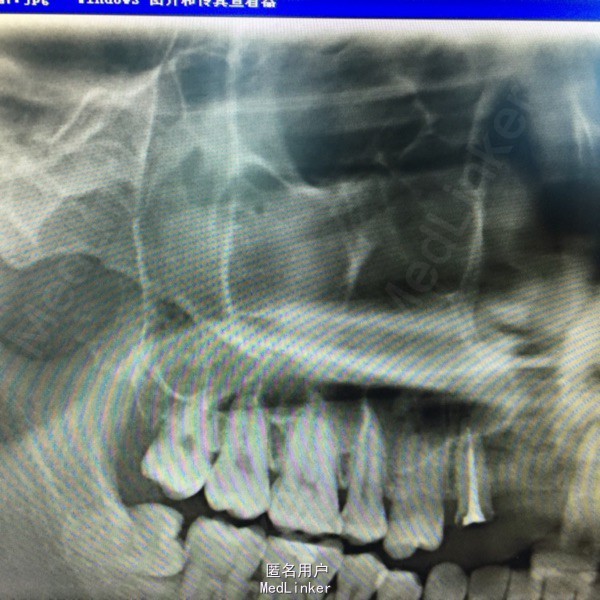

上前牙烤瓷冠修复,13牙冠缺损,叩(+),行桩冠修复。曲面断层片示:13、14根尖可见4x2cm阴影,边缘可见白色阻射线。

诊断:13、14根尖囊肿 处理:1、拆除桩冠。 2、13行牙髓治疗。 3、囊肿行开窗引流术。

患者每天以生理盐水冲洗,2一4次/天,半年复查X片。 该患者1年半后,可见囊腔缩小,新骨长入。无需行囊肿挖除术。